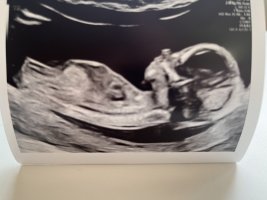

Dette er en tydelig jente! Ultralyd er jo snitt av kroppen, det betyr at ikke alt er synlig samtidig og da kan jo f.eks deler navlestreng eller lårbein eller en hånd som stikker ned se ut som noe er mellom beina litt her og der. Hvis du er 14 uker så hadde du sett en ganske tydelig penis nå. Hos gutter ser man gjerne at blæren er mye lavere hvis penis ikke skulle blitt med på bilde.Mulig å se noe her? Syntes jeg så en tydelig snopp på ultralyden, men jordmoren sa hun holdt en finger på jenteMålt til 14+0

Var på ul i dag.ÅååDette er en tydelig jente! Ultralyd er jo snitt av kroppen, det betyr at ikke alt er synlig samtidig og da kan jo f.eks deler navlestreng eller lårbein eller en hånd som stikker ned se ut som noe er mellom beina litt her og der. Hvis du er 14 uker så hadde du sett en ganske tydelig penis nå. Hos gutter ser man gjerne at blæren er mye lavere hvis penis ikke skulle blitt med på bilde.